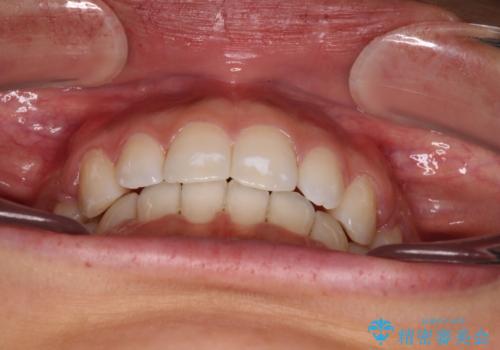

2年から2年半の治療期間を想定しており、予定通りの期間で無事に終了することができました。

唇や顎先に力を入れないなくてもスムーズに唇を閉じることができるようになりました。